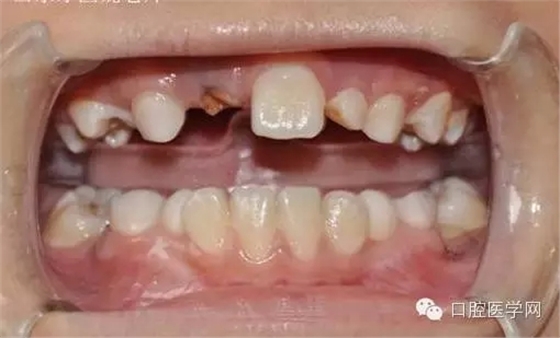

基本資料:男8歲、祖籍山東滕州、二年級(jí)。

主訴:門牙遲遲不長

現(xiàn)病史:右乳上一牙根滯留。

小兒8歲發(fā)現(xiàn)右上門牙遲萌,右乳一殘根。